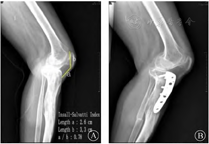

注: A为IS指数示低位髌骨。B为术后侧位片,Tomofix钢板纵轴与胫骨纵轴平行,髌骨位置较术前无明显降低.

综合考虑,本例选择单平面LCWHTO,使用Miniaci法[18]将下肢力线过度矫正到Fujisawa点(图4) ,在充分矫正畸形的同时,避免了低位髌骨、内侧瘢痕处皮肤坏死的发生,通过自身骨的加压接触,实现截骨端早期愈合,加速患者的康复进程。